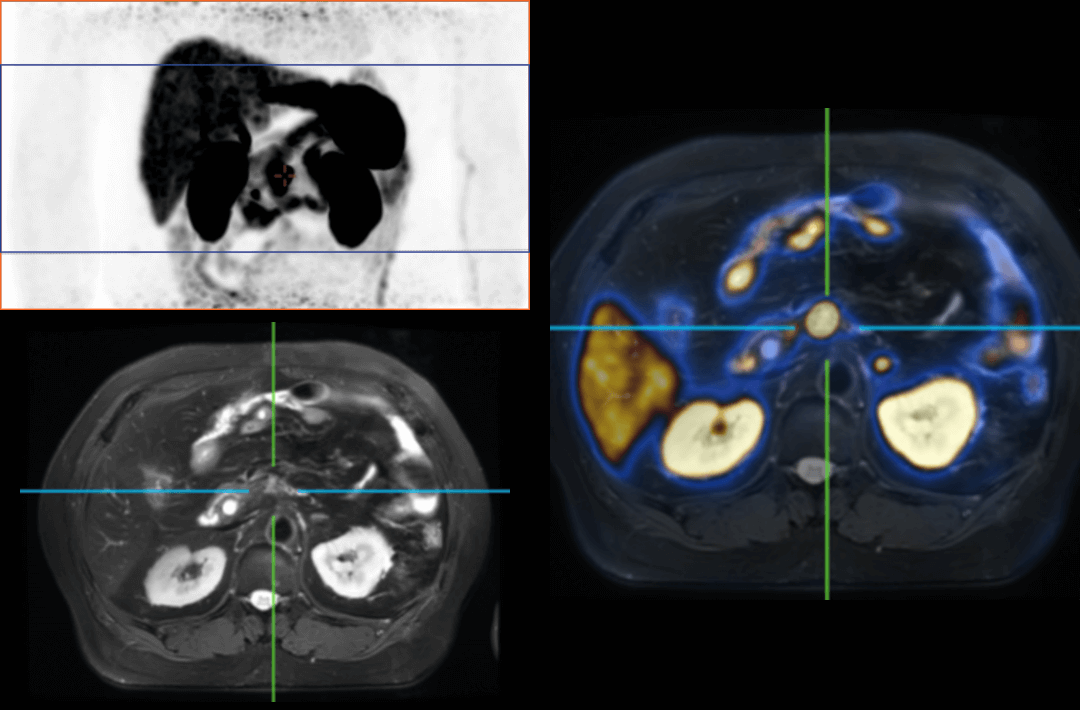

PET/MRは分子機能と構造画像を完全に結合し、腫瘍、心血管疾患、神経疾患、小児疾患、炎症性疾患の臨床診断に欠かせない手段として役立っています。

AFOVが、従来の20cm~25cmのPET装置と比較して、32cmの長尺AFOVであることにより、感度が向上するだけでなく、全身の主要臓器や転移が考えられる局所リンパ系において1ベッドポジションでがんのTNステージを実現することが可能となります。

2019年8月、Peking Cancer Hospitalはユナイテッド イメージング ヘルスケアのPET/MRを導入し、長いAFOV下でのがんTNM病期決定の徹底的な探求と最適化を行いました。500例以上の様々な臓器のスキャンにより、長い AFOV PET/MRは1つのベッドポジションでのスキャン範囲を大幅に拡大し、がんTNMステージングの効率を向上させることができることが証明されました。

乳がん、食道がん、前立腺がんなどのTNMステージングを「時空間統合」ULTRA-clear TOF PET/MRの長軸視野で最適化した事例を紹介します。